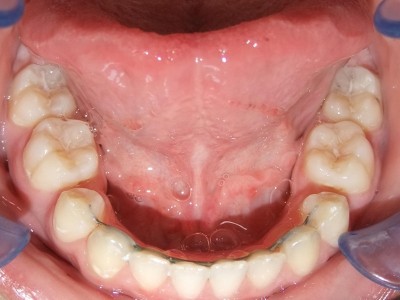

Retentie fase: Wrap en C-CBar

Voor behandeling

Na behandeling